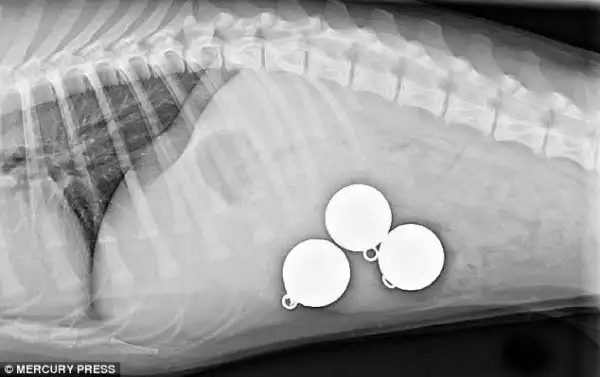

Лабрадор, проглотивший 3 массивных рыболовных грузила

Три 200-граммовых грузила извлеченные из его желудка